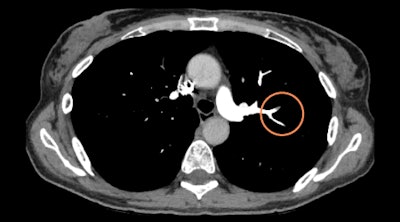

Aidoc's pulmonary embolism detection algorithm flags CT angiograms for urgent review. Image courtesy of Aidoc.

Aidoc's pulmonary embolism detection algorithm flags CT angiograms for urgent review. Image courtesy of Aidoc."The solution has a proven track record of integrating in over 150 different IT architectures and is agnostic to PACS, workflow solutions, and modalities used -- providing notifications directly in the radiologist's working environment with no need for the radiologists to change the way they work or perform extra clicks," Walach told AuntMinnie.com.